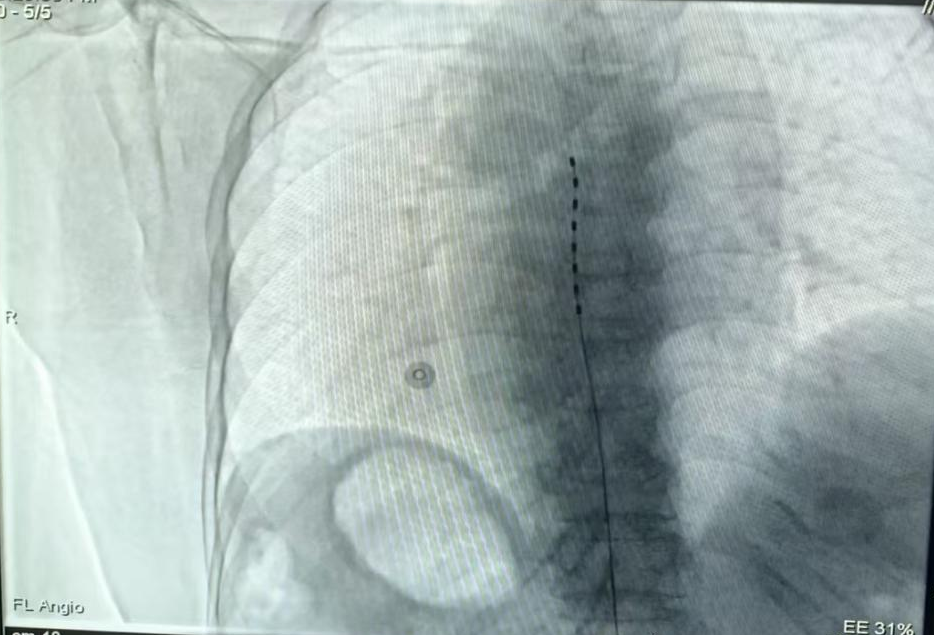

经过完善的术前准备,手术如期进行。在先进的数字减影血管造影(DSA)引导下,医疗团队为患者进行了局部麻醉。手术团队凭借精湛的技术,通过微创穿刺,将刺激电极精准植入到目标脊髓节段(T8-T11水平)的硬膜外腔,覆盖疼痛对应的神经传导路径。

术中,团队进行了至关重要的电刺激测试。通过体外遥控器反复调整电极组合、电压、脉宽及频率等参数,直至产生的微弱电流完全覆盖患者原有的疼痛区域,且无任何不适。测试成功后,将电极妥善固定。整个手术过程顺利,出血极少,患者生命体征始终保持平稳。